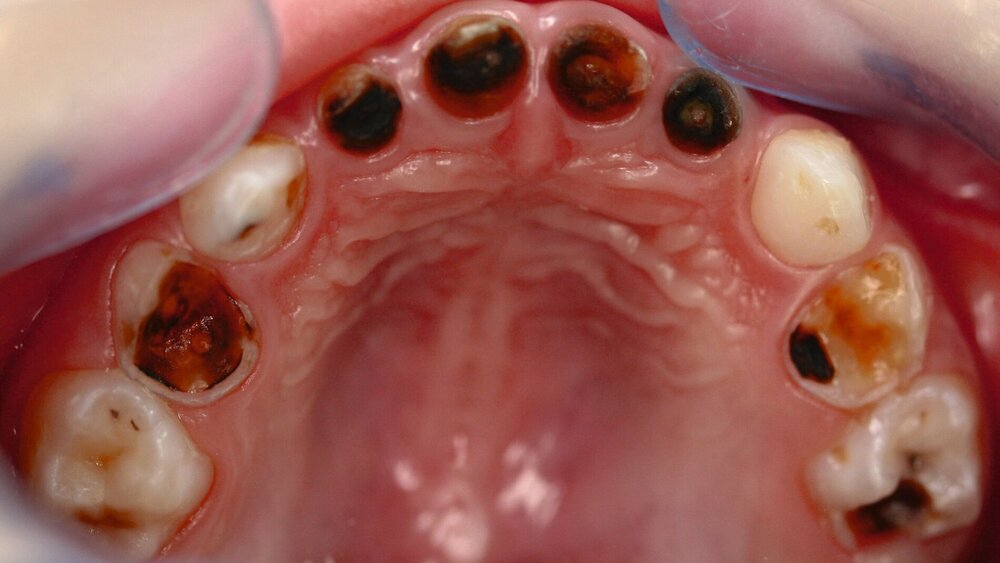

Karies an Milch- und bleibenden Zähnen stellt ein chronisches Ungleichgewicht mit überwiegendem Mineralverlust dar. Daraus ergibt sich eigentlich schon die Richtung einer ursächlichen Therapie: die Umkehrung zur Remineralisation. Dies bietet sich gerade bei kleinen Kindern mit Milchzähnen an, die dann später ohne zwingende Notwendigkeit einer restaurativen Therapie exfoliieren können. Die Läsionen können „einfach“ inaktiviert werden, was durch eine verbesserte tägliche Mundhygiene und durch Fluorideinsatz sehr wirkungsvoll erzielt werden kann (Abbildung 1).

Die (häusliche) Kariesinaktivierung bietet hier einen biologischen, ursächlichen Ansatz: Gerade bei offenen, kariösen Defekten ohne irreversible pulpale Schädigung kann sie zum Beispiel bei jüngeren Angstpatienten als non-invasive Kariestherapie ohne Bohrer [Santamaria et al., 2015], Zange oder gar Narkose dienen [Hansen und Nyvad, 2017]. Dabei sind regelmäßige Mundhygienemaßnahmen und eine risikogerechte Zufuhr an Fluoriden essenzielle Bausteine der Therapie (Abbildung 1).